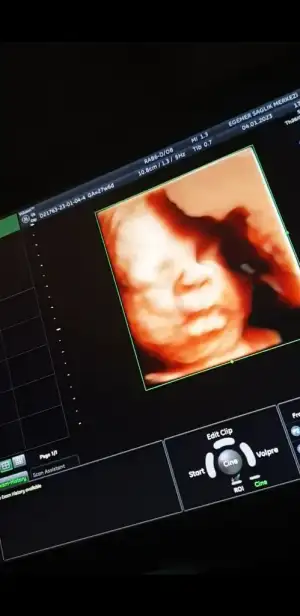

37,5cm 1,5kg olmuşuz ve doğum pozisyonundaymış minnoş :) ben hareketlerinden ve rahim ağzında ki baskıdan anlamıştım zaten. Herşey yolundaymış bizde. İnşallah sizlerde de güzeldir :))